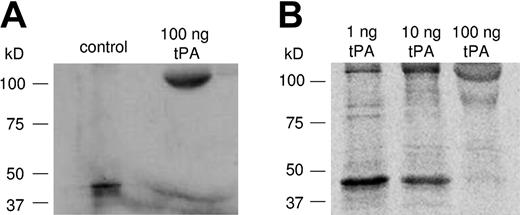

To investigate to what extent the newly synthesized PAI-1 was active, a functional assay was performed in which platelets were incubated with 35S-methionine in the presence of increasing tPA concentrations. PAI-1 as well as the tPA/PAI-1 complex was detected by immunoprecipitating with the MAI-12 antibody. Figure 4A shows the result of 2 platelet incubations; the first is a control without tPA present and the second is with 100 ng tPA. Incubation with a molar excess of 100 ng tPA resulted in a different migration position corresponding to the expected position of the tPA/PAI-1 complex. This finding indicated that the newly formed PAI-1 was in an active configuration. As shown in Figure 4B, addition of increasing concentrations of 1-10-100 ng tPA resulted in a gradual diminution of free PAI-1 protein.

Functional analysis of the activity of newly synthesized PAI-1. Platelets were incubated in the presence of 1, 10, and 100 ng tPA for 6 hours as described in Figure 3. (A) Addition of 100 ng tPA resulted in a different migration position corresponding to the expected position of the tPA/PAI-1 complex, indicating that newly synthesized PAI-1 is active. (B) Addition of increasing concentrations of tPA reduced the free PAI-1 protein and increased the tPA/PAI-1 complex.

Functional analysis of the activity of newly synthesized PAI-1. Platelets were incubated in the presence of 1, 10, and 100 ng tPA for 6 hours as described in Figure 3. (A) Addition of 100 ng tPA resulted in a different migration position corresponding to the expected position of the tPA/PAI-1 complex, indicating that newly synthesized PAI-1 is active. (B) Addition of increasing concentrations of tPA reduced the free PAI-1 protein and increased the tPA/PAI-1 complex.